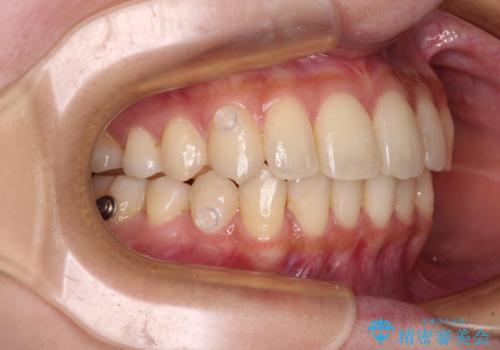

- 前歯のデコボコと強い咬みしめを気にして来院された患者様です。

インビザラインを用いて、前歯の叢生を解消するとともに、ディープバイトを改善していくこととしました。

海外へ転居する予定があったため、1日22時間以上の装着時間をしっかりと守っていただき、予定期間よりも早く、思っていた以上にきれいに仕上げることができました。